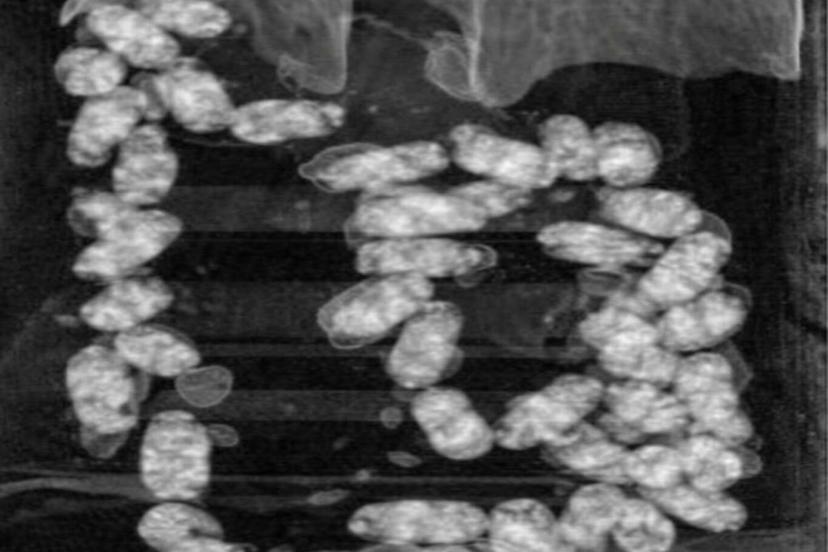

Narkotik Suçlarla Mücadele Şube Müdürlüğü ekiplerince yurt dışından İzmir’e "yutmak" suretiyle uyuşturucu madde getirilmesi üzerine operasyon başlatıldı.

Yapılan teknik ve fiziki takip sonucunda kimlikleri tespit edilen şahıslar, İzmir Adnan Menderes Havalimanı’nda yakalandı.

Şüpheliler üzerinde yapılan iç beden muayenesinde, 105 kapsül halinde yutulmuş vaziyette toplam 965 gram metamfetamin ele geçirildi.

Operasyon kapsamında gözaltına alınan iki şüpheli emniyetteki işlemlerinin ardından sevk edildikleri mahkemece tutuklandı.